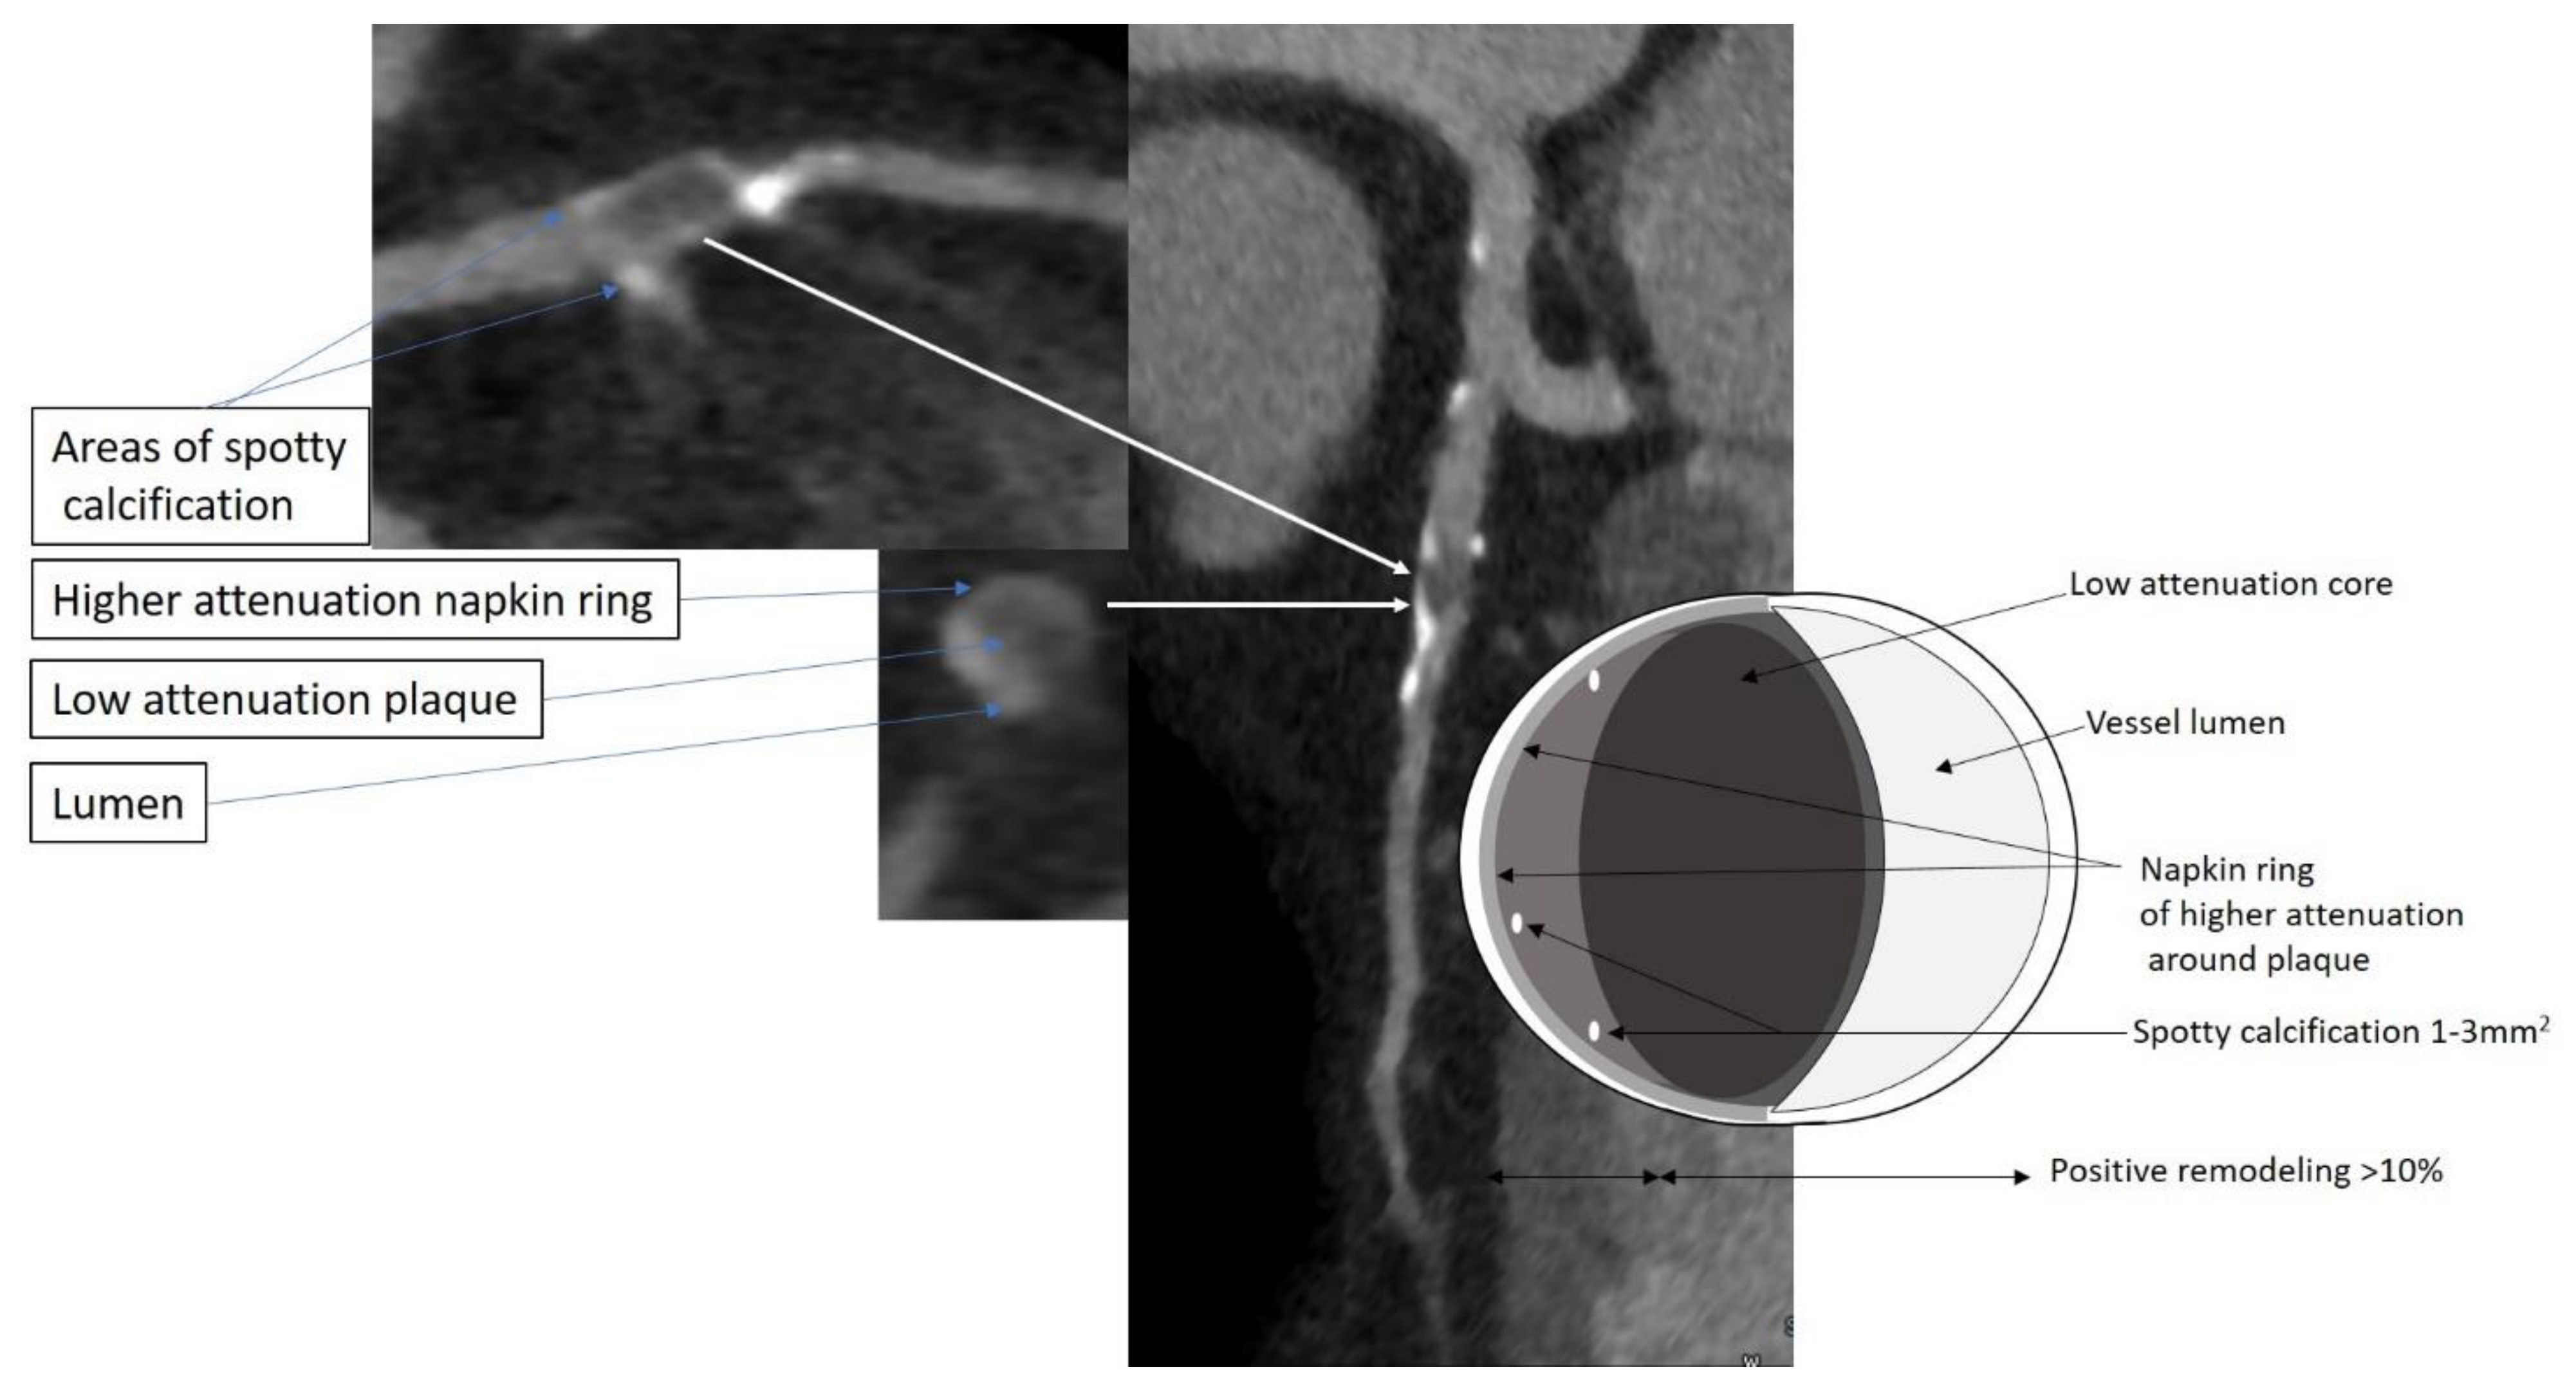

- Ferencik, M.; Mayrhofer, T.; Bittner, D.O.; Emami, H.; Puchner, S.B.; Lu, M.T.; Meyersohn, N.M.; Ivanov, A.V.; Adami, E.C.; Patel, M.R.; et al. Use of High-Risk Coronary Atherosclerotic Plaque Detection for Risk Stratification of Patients with Stable Chest Pain: A Secondary Analysis of the PROMISE Randomized Clinical Trial. JAMA Cardiol. 2018, 3, 144–152. [Google Scholar] [CrossRef] [PubMed]

- Williams, M.C.; Moss, A.J.; Dweck, M.; Adamson, P.D.; Alam, S.; Hunter, A.; Shah, A.S.V.; Pawade, T.; Weir-McCall, J.R.; Roditi, G.; et al. Coronary Artery Plaque Characteristics Associated With Adverse Outcomes in the SCOT-HEART Study. J. Am. Coll. Cardiol. 2019, 73, 291–301. [Google Scholar] [CrossRef]

- Williams, M.C.; Kwiecinski, J.; Doris, M.; McElhinney, P.; D’Souza, M.S.; Cadet, S.; Adamson, P.D.; Moss, A.J.; Alam, S.; Hunter, A.; et al. Low-Attenuation Noncalcified Plaque on Coronary Computed Tomography Angiography Predicts Myocardial Infarction: Results From the Multicenter SCOT-HEART Trial (Scottish Computed Tomography of the HEART). Circulation 2020, 141, 1452–1462. [Google Scholar] [CrossRef]

- Virmani, R.; Burke, A.P.; Kolodgie, F.D.; Farb, A. Vulnerable plaque: The pathology of unstable coronary lesions. J. Interv. Cardiol. 2002, 15, 439–446. [Google Scholar] [CrossRef]